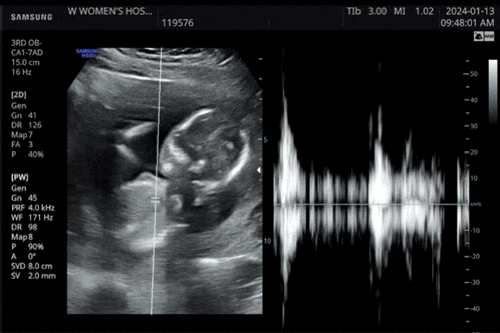

임신 26-28주차 일상 : 입체초음파, 베이비페이스, 배 크기, 증상, 첫 강릉 태교여행

허허..내일되면 8개월 진입 실화..? 한달 주기 검진도 2주로 줄어들었다.. 26-28주차 증상 모음 ? 1. 더...